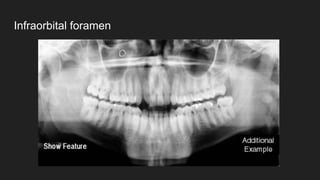

● Infraorbital foramen

Infraorbital foramen